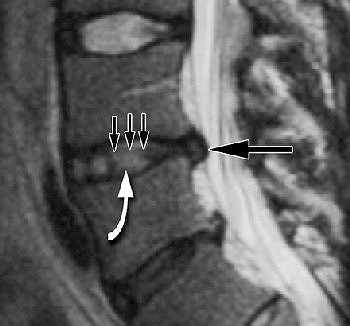

| Grade II disk degeneration with recurrent disk herniation. T2-weighted sagittal MR image (5000/130) obtained in 41-year-old man in study group with lumbar disk herniation (long black arrow) at the L4-5 level before primary diskectomy. Disk degeneration was rated as grade II because an inhomogeneous bright nucleus pulposus (white arrow) with hypointense bands (short black arrows) was seen. Figure 3, Dora C, Schmid MR, Elfering A, Zanetti M, Hodler J, Boos N, "Lumbar disk herniation: Do MRI findings predict recurrence after surgical diskectomy?" Radiology 2005; 235:562-567. |

According to the results, all 60 patients had at least one disk extrusion at preoperative MR imaging, as well as neural compromise. Advanced disk degeneration (grades IV and V) occurred more frequently in the control group. No disk degeneration or minor degeneration was seen before initial surgery in 83% of the study group and 50% of the control group.

"The risk of recurrent disk herniation was reduced by a factor of 3.4 for each increase in the grade of disk degeneration," the authors explained. "A normal intervertebral disk (grade II at MR imaging) in an adult has a 6.8-fold increase in the risk of recurrent herniation, as compared with the risk of a disk with advanced degeneration (grade IV)."